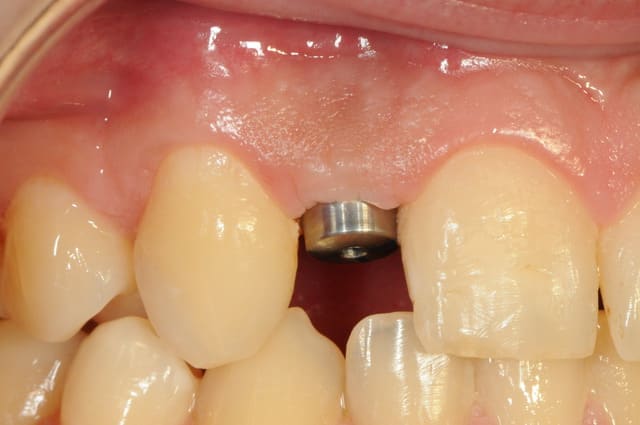

-cicatrisation de la première vis de cica,

-diamètre plus gros pour la vis de cica

- pilier pour la provisoire

- provisoire moule ION

- ajustage

- polissage soigneux

la suite tout à l'heure, ça sonne à la porte...